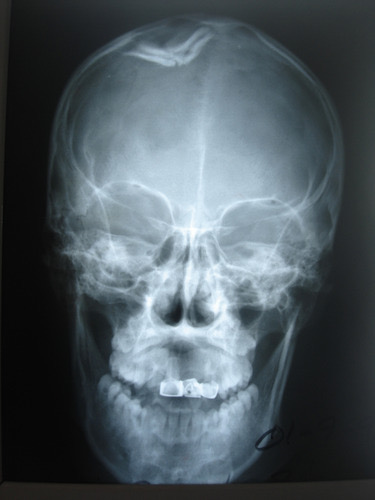

The skull is part of the _ skeleton

axial

Cleft lip and palate

Bones of the mouth do fuse properly. Birth defect